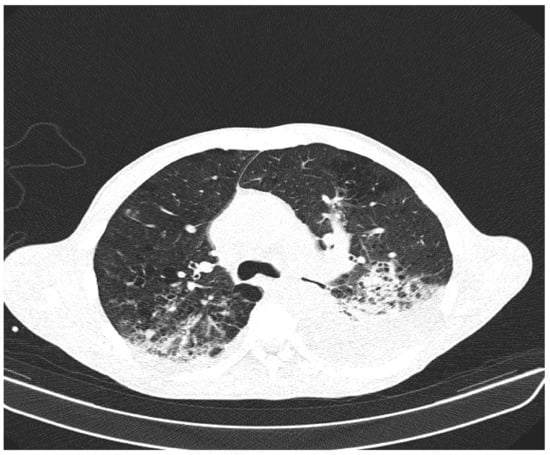

Due to the worsening general conditions, the patient was submitted to thoracic, abdominal, and pelvic computer tomography scans, which revealed:

• Numerous central and peripheral emphysema bubbles, with regular thin walls, located at the level of both lung fields, the largest located apically superior bilaterally;

• Numerous bronchiectasis with variable dimensions, some with free lumen, located in both upper lobes, in the right middle lobe and lingular segments;

• Pulmonary condensation areas in the middle and posterobasal segments of both lower lobes, especially on the left side (Figure 4).

Figure 4. Patient’s computer tomography: pulmonary condensation areas in the middle and posterior-basal segments of both lower lobes, especially on the left side.